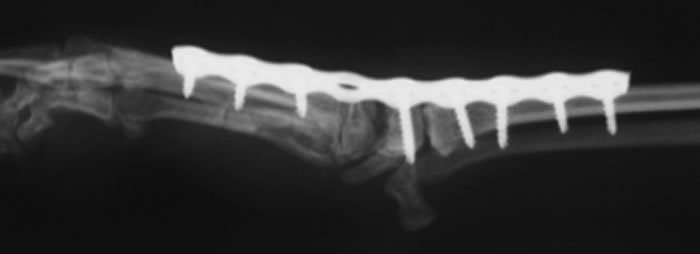

手根関節脱臼 / 亜脱臼 / 不安定症 / 過伸展

手根関節脱臼 / 亜脱臼 / 不安定症 / 過伸展とは

落下やジャンプに伴って起こる靭帯損傷や、免疫介在性関節炎、糖尿病、クッシングなど内科疾患に関連して起こる靭帯変性により生じる手根関節の不安定性

レントゲン検査など

治療

外科適応の場合は全関節固定術、部分関節固定術、スーチャーアンカー法などをおこない、手根関節を固定します